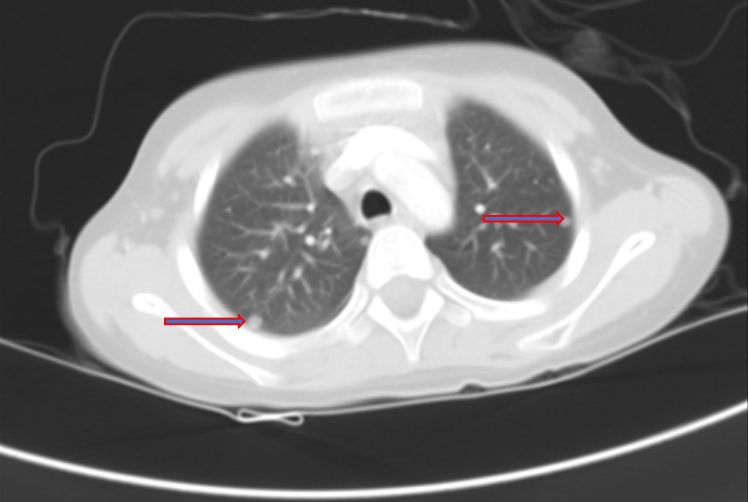

2程化疗后复查CT示:肝右叶病灶缩小,约7.1×8.0cm,肝右静脉、下腔静脉内病灶,双肺转移瘤病灶范围较前缩小。

图3 两程化疗后复查CT